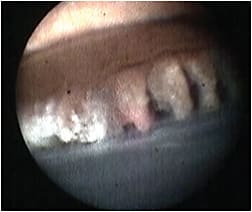

Viscoelastic should be completely removed by irrigation and aspiration to prevent postoperative IOP spikes. OR staff need to adjust the handpiece where it connects to the laser console in order to focus, adjust power and light, and rotate the image if necessary. The procedure is performed while looking at a monitor (Figure 4, page 19), which needs to be positioned so that the surgeon can view it without turning away from the patient. To avoid inflammation, steroids are given intravenously, intracamerally, subconjunctivally, or orally during or after the procedure in addition to frequent topical administration. The reusable probes are fragile, and bending them damages the fiberoptic cables leading to degradation of the surgical view.